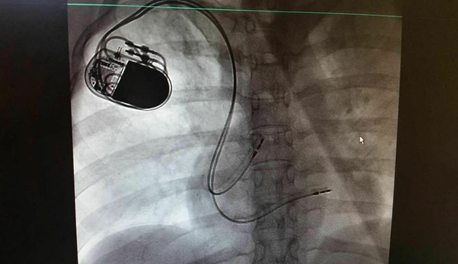

4月初,北京博爱医院心脏内科团队成功植入一例抗核磁共振心脏起搏器。

患者在家属及医护人员的陪同下前往导管室,抗核磁心脏起搏器成功植入患者体内,过程顺利。术后患者生命体征正常,心率稳定在在60次/分以上,患者心脏缺血症状明显好转,给予患者床旁早期临床康复。此例起搏器的植入不仅解除了患者心动过缓的症状,也为患者在将来的康复治疗及核磁检查提供了安全的保障,提高了患者的生活质量。